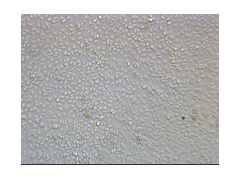

A2780/Taxol细胞- A2780/Taxol耐药株;人卵巢癌紫杉醇耐药株 上皮细胞 贴壁生长

采用体外低浓度梯度递增联合大剂量间断冲击方法诱导肿瘤细胞对药物产生耐药性

MTT法测定药物对亲本细胞和耐药细胞的IC50,计算耐药指数